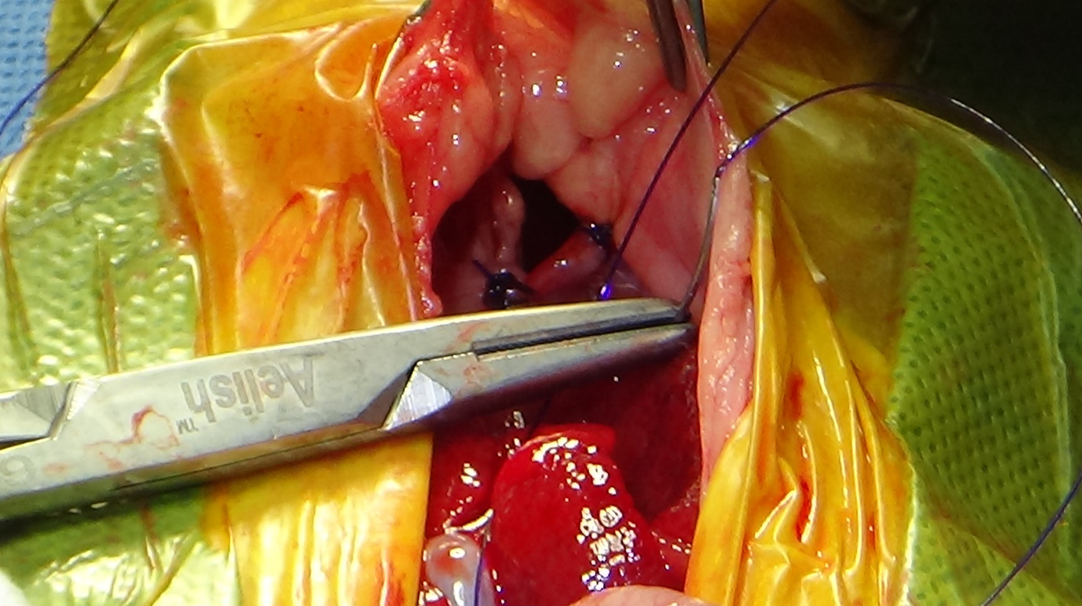

수술은 삼각형 모양의 횡격막 결손, 벌어져 융합되지 않은 caudal sternebrae를 확인할 수 있는 복부 정중 절개로 시행되었습니다.

탈장이 일어난 장기를 정상 위치로 되돌리고, 횡격막 결손은 등쪽에서부터 배쪽으로 단순 연속 봉합법을 통해 폐쇄했습니다.

봉합 후 흉강에 음압을 걸고, 복강을 세척하면서 다시 한번 횡격막의 완전성을 확인했습니다.